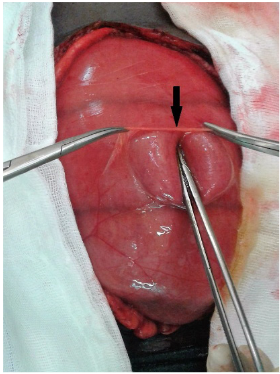

Se intervino quirúrgicamente de urgencia, identificándose gran distensión del intestino delgado desde el ligamento de Treitz hasta el íleon terminal, con una hernia paraduodenal izquierda como etiología de la obstrucción intestinal (Figura 2). Se hizo reducción del intestino delgado herniado y cierre del orificio herniario con sutura continua no absorbible (Figura 3). La evolución del paciente fue favorable.

Figura 2. Transoperatorio. La flecha muestra el saco herniario abierto con distensión de asas intestinales delgadas.